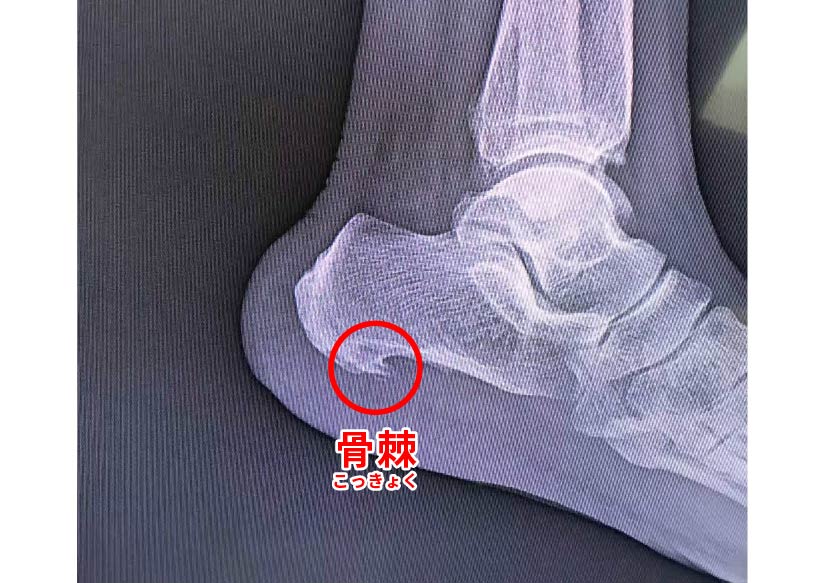

足底筋膜炎(足の前部とかかとを繋ぐ靱帯である足底筋膜の変性炎症)を患っている場合は、舗道を歩いたり、ベッドから起き上がったりするときに、このかかとの不快感がどれほど痛いかをご存知でしょう。